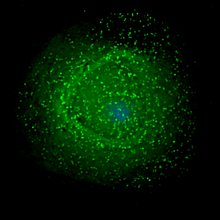

| Scanning electron micrograph of HIV-1 (in green) budding from cultured lymphocyte. Multiple round bumps on cell surface represent sites of assembly and budding of virions. | |